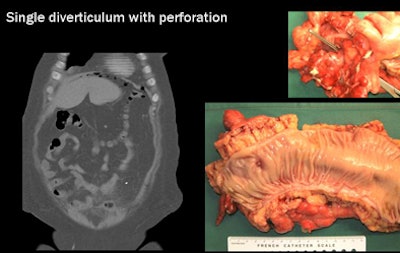

Importantly, "CT has the highest sensitivity for tiny air bubbles, which would not be detected on a conventional x-ray, ultrasound, or MRI," he said. "That's why CT is so important in this disease to detect the complications."

![]() |

| CT's most important advantage in imaging diverticular disease is its high sensitivity for air bubbles indicating colonic perforation. At left, bubble at CT reveals a single perforation in the colonic mucosa, confirmed in postsurgery specimen (right). |